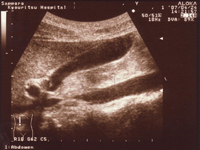

超音波診断で観察できる臓器の様子

胆のう

肝臓・腎臓

大動脈部位